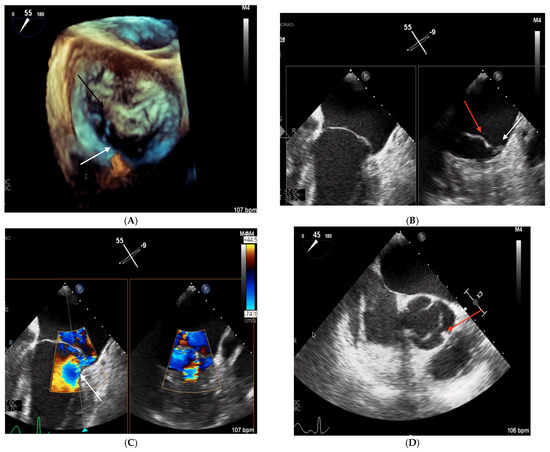

2.1. Clinical Case 1